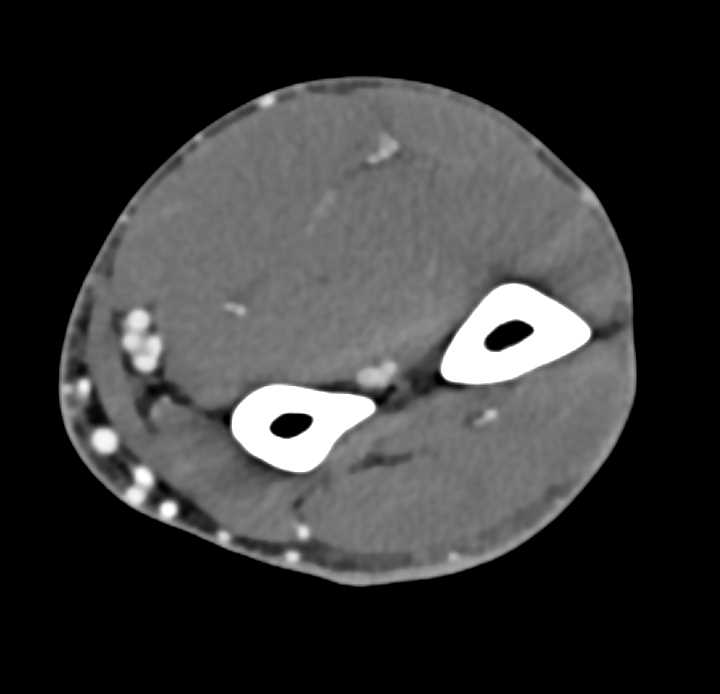

Forearm abscess | Image | Radiopaedia.org

Swelling of the left arm, the left forearm, and the right wrist …

Calf Abscess|Causes|Symptoms|Treatment|Home Remedies|Recovery|Prognosis